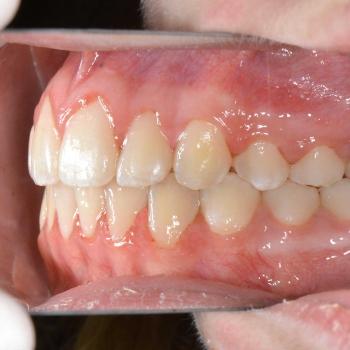

A kezelés megoldotta az összes fogszabályozással kapcsolatos problémát, így egy funkcionálisan és esztétikailag is megfelelő harapást kaptunk.

A kezelés teljes időtartama: 2 év